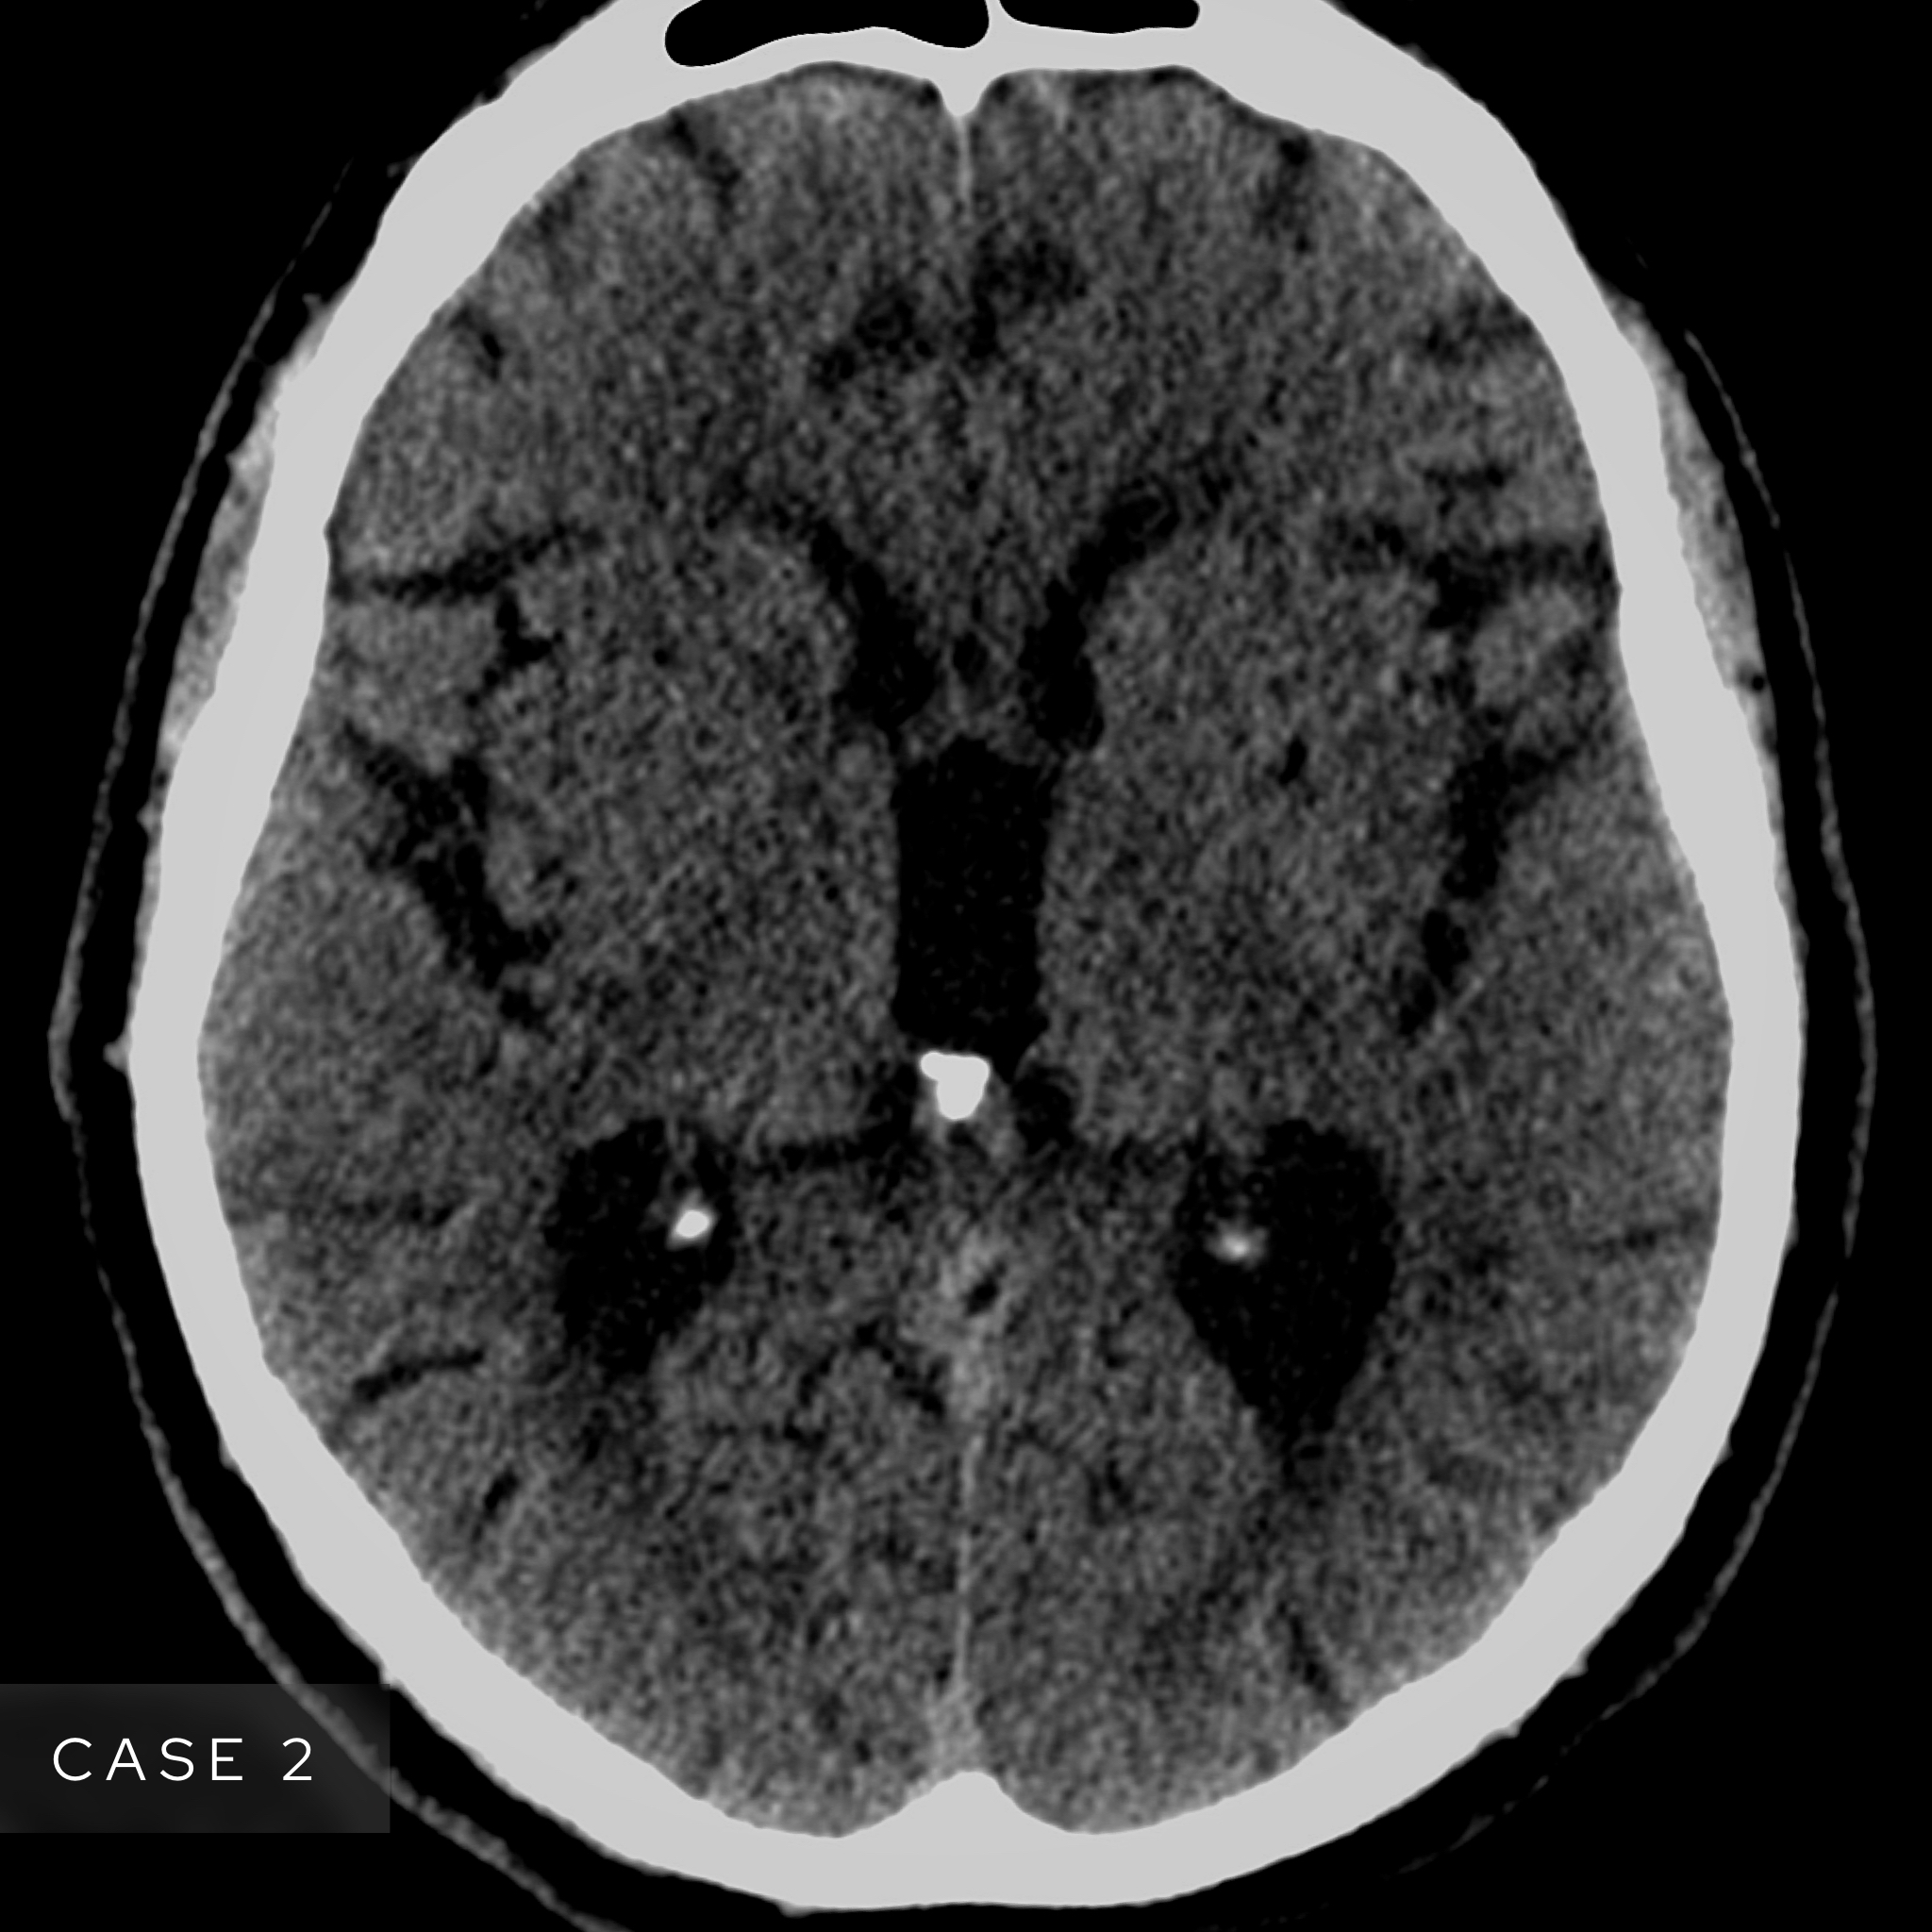

Case 2

A male in his 70s presents with right sided weakness. Have a look at this image from a non contrast CT head. What best describes the finding and most likely diagnosis?

Choose from one of the following options: